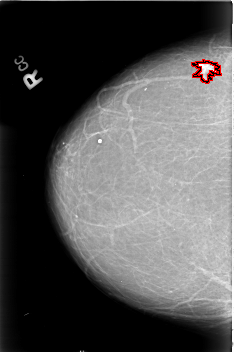

B_3022_1.RIGHT_CC

RIGHT_CC LINES 4568 PIXELS_PER_LINE 3032 BITS_PER_PIXEL 12 RESOLUTION 50 OVERLAY

FILE: B_3022_1.RIGHT_CC.OVERLAY

TOTAL_ABNORMALITIES 1

ABNORMALITY 1

LESION_TYPE MASS SHAPE IRREGULAR-ARCHITECTURAL_DISTORTION MARGINS SPICULATED

ASSESSMENT 5

SUBTLETY 5

PATHOLOGY MALIGNANT

TOTAL_OUTLINES 1

BOUNDARY